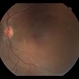

- preeclampsia, choroidal infarction

- Imaging device

- Fundus camera

- 66-year-old Hispanic female with a history of severe preeclampsia at age 45. This photograph shows faint gray choroidal scars. Seen better on FA (in gallery).